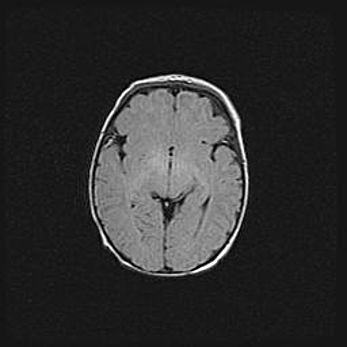

Церебральная ишемия II.

Возраст: 7 дней

Вес: 3350 г

Пол: женский

Окружность головы: 35 см

Срок гестации: 39 недель

Ишемия головного мозга – это состояние, которое развивается в ответ на кислородное голодание вследствие недостаточного мозгового кровообращения. У новорожденных она является следствием дефицита кислорода, что ведет к метаболическим расстройствам различной степени тяжести в тканях головного мозга, в том числе к развитию коагуляционных некрозов и гибели нейронов.